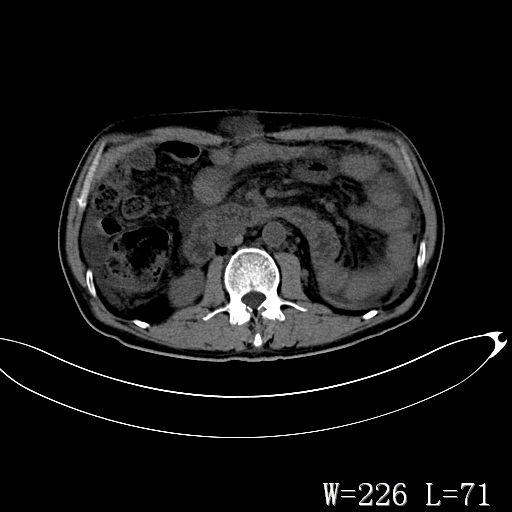

男,52岁,门脉高压断流术后1年,发现腹部肿物2月。

1)前腹壁中线区(脐上方)囊性占位性病变,考虑淋巴囊肿。2)腹水。